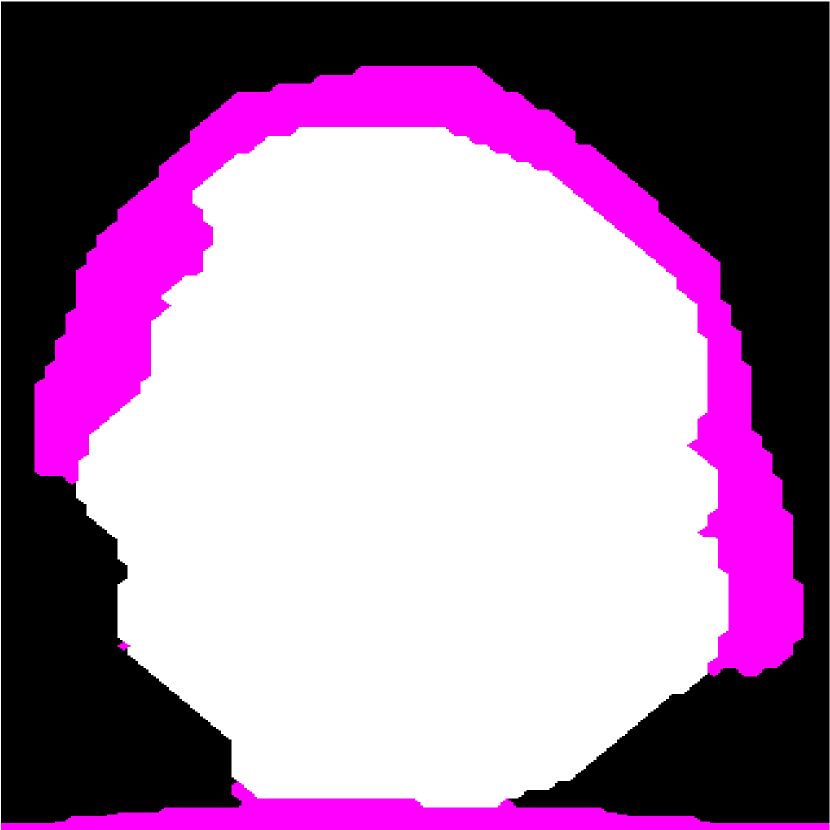

Figure 1: (a) Target HFU image. (b) Manual-segmentation result by an expert. LNP is white and fat region is pink. The vertical axis is depth. (c) The segmentation result obtained by K-means.

In addition to intensity information, we take advantage of structural information. As shown in Figure 1(b), LNP, fat, and PBS are in a nested configuration. Some approaches based on graph cuts (GCs) can segment multiple objects at the same time and preserve some structural relationship between these objects in the segmentation result. Ishikawa described representing different objects by separate layers of a graph, and showed that a multi-object segmentation problem can be solved as a binary GC problem if the energy term satisfies certain convex conditions [8]. Although objects in the segmentation result under his structure have a nested relationship, he did not consider how to take advantage of it. To exploit the known generic relationships between objects (e.g., containment, attraction, and exclusion), Delong and Boykov described a multi-region GC [9]. However, Delong and Boykov’s model requires manually selected seeds to define the missing boundary between objects with similar intensity distributions. In order to deal with the missing boundary in a nested structure automatically, Kuo et al. described nested graph cut (NGC) [10]. In NGC, the missing boundary of an inner object can be defined by the convex hull of its outer object automatically. Kuo et al. applied NGC to segmenting LNs and overcame the missing boundary between LNP and PBS [11]. Level-set-based approaches also can be used to preserve the nested relationships in segmentation processing. Nosrati et al. described a level-set version [12] of Delong and Boykov’s model. In addition, multiphase level-set approach also works well to preserve nested relationships by deforming multiple, non-crossing, nested, level-set functions. Bui et al. described a 3-phase, level-set method to segment LNs [13]. Compared to GC-based methods, level-set-based methods can avoid grid bias and can permit faster calculations, but they require proper initialization or initial seeds to avoid converging to a local minimum. In a more-recent work, Bui et al. [14] used random-forest classification to pre-segment images and initiate a level-set approach.

Figure 2: (a) Target HFU image. (b) Manual-segmentation result. (c) The segmentation result obtained by NGC with depth-dependent profile.

Intensity-distribution estimation is another challenge in LN segmentation. To obtain satisfactory segmentation, accurate intensity distributions for the three components of isolated LNs are required. Some clustering algorithms, such as K-means or expectation maximization (EM), may be able to categorize the intensity values of all voxels into three distributions to represent target objects. However, these approaches often yield unsatisfactory segmentation results for larger LNs (Figure 1(c)), where the intensity distribution fluctuates significantly with depth because of acoustic attenuation and focusing effects. In addition, attenuation effects may become so extreme that fat boundaries become invisible. (See the red arrow in Figure 1(a).) To mitigate the attenuation and missing-boundary problems, we used depth-dependent intensity profiles to model the depth-dependent variation of intensity mean and standard deviation in our prior work [11]. Using an expectation-maximization (EM) -based iterative framework, depth-dependent profiles were estimated by a spline-based fitting process from the previous segmentation result, and the segmentation result was obtained by NGC using the estimated depth-dependent profiles. Instead of using an EM-based framework to update profiles, level-set-based approaches can also update profiles during deformation. Bui et al. developed a method, which applied depth-dependent profiles, called statistical transverse slice level-set (STS-LS) [15]. Nevertheless, depth-dependent profiles are unable to deal with intensity inconsistency within the same depth caused by inhomogeneous acoustic attenuation as shown in Figure 2. Figure 2(c) shows the segmentation result obtained using a depth-dependent profile [11]. Compared to the manual segmentation result in Figure 2(b), some fat regions (red arrow) are mislabeled as LNP because the fat on the right (green arrow) at the same depth is much brighter than the fat on the left. In this case, depth-dependent profiles are unable to model the intensity variations accurately. Using local distribution to differentiate LNP and the fat can solve the error caused by intensity inconsistency within the same depth. Bui et al. has used a local-region-based, gamma distribution to segment LNs [13]. Level-set-based methods is good in applying local intensity distributions to differentiate regions. Since level-set-based methods deform the contour gradually, the local distributions can be updated by the boundary accordingly. However, updating distributions in local regions is computationally expensive. Furthermore, using local-region-based distributions with level-set-based methods is likely to result in convergence to a local minimum when the image is noisy. In contrast, GC-based approaches generally set the similarity cost by predefined intensity distributions. Because the boundary is unknown, the local region is hard to be determined in advance.